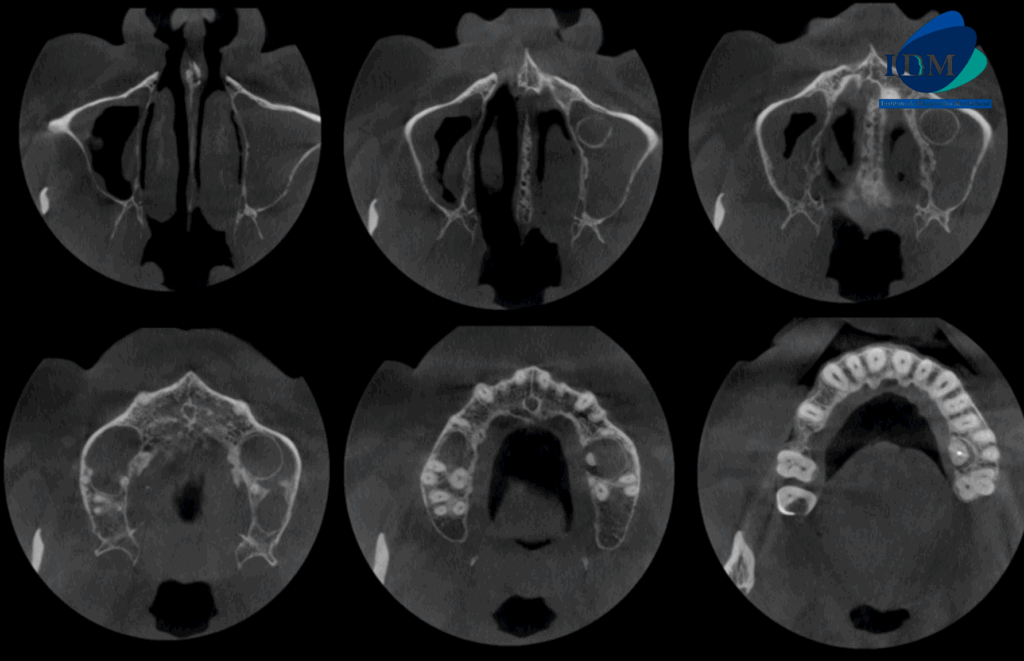

A la evaluación de la tomografía computarizada en cortes axiales, transaxiales y tangenciales se observa la pieza 16 con la raíz mesiovestibular con una obturación parcial y sobre extendida del conducto, asimismo presenta un conducto colateral obliterado y un proceso osteolítico periapical y reabsorción radicular externa del tercio apical; la raíz distovestibular presenta también una obturación parcial de conducto y la raíz palatina presenta un espigo intrarradicular, obturación parcial y subextendida del conducto y una imagen hipodensa corticalizada que desplaza hacia cefálico el piso de seno maxilar y compromete la tabla ósea palatina compatible con quiste radicular, asimismo ocasiona un engrosamiento de la mucosa antral ipsilateral compatible con sinusitis de origen odontogénico.

CORTES AXIALES